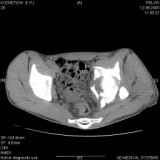

Уважаемые коллеги! Хотелось бы услышать совет по тактике лечения представлленого больного.Поступил после лечения в одном изотделений области. Травма 2,5 месяца назад. После выведенияиз шока был произведен остеосинтез перелома бедра, предплечья, до перевода к нам проводилосьвытяжение по оси шейки бедра за стержень, введенный в большой вертел. На сегодня деформацияригидна, клинически мобильности не определяется. Заранее признателен. P.S. Данный вид травм не включен в перечень "высокотехнологичных операций", направить длялечения по квотам Минздрава очень сложно.

Привет, Леонид. Оскольчатый высокий двухколонный перелом в такие сроки трогать не надо, т.к. это про такие переломы сказано: "кто с ножом на Ж. пойдет тот в ней и останется...".